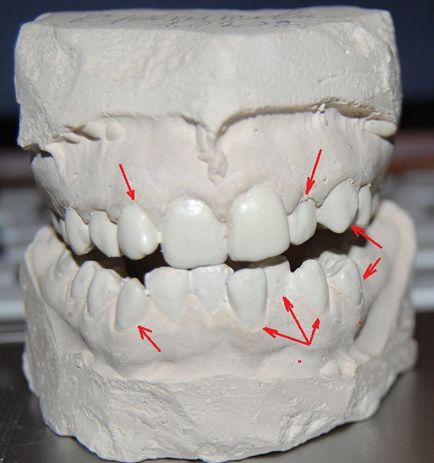

Most esetem. Bizonyára, ha szeretné tudni, hogy mi történt előtte és utána lett. Azt kényezteti ezeket a képeket)) Mielőtt a telepítés fogszabályozó orvos mindig teszi a gipsz, az állkapocs, számomra a kezelés végén mutatták be)

Vehrnyaya állkapocs és harapás. Kettesével balra (akik az erdőben, akik tűzifa), harapás egy kicsit előre, agyarait telepített

Az alsó állkapocs. Ez mind nagyon rossz. Két kúszott végig tripla ment vissza eredetileg rés (két hely nem elég), szemfogak egyaránt erősen telepített, egy még őrölni le a felső fogak. Ott van még a gyökér séta Arc.

Offset három síkban - a saját tengelye körül, oda-vissza, jobbra és balra. Mielőtt a nadrágtartó, mentem két orvos. Először azt javasolta, hogy kicsikarni 4 fog egyszerre az ajánlatot elment a fürdőbe. Én fix minden nélkül foghúzás és 8 év után nem fáj, és nem tért vissza újra.